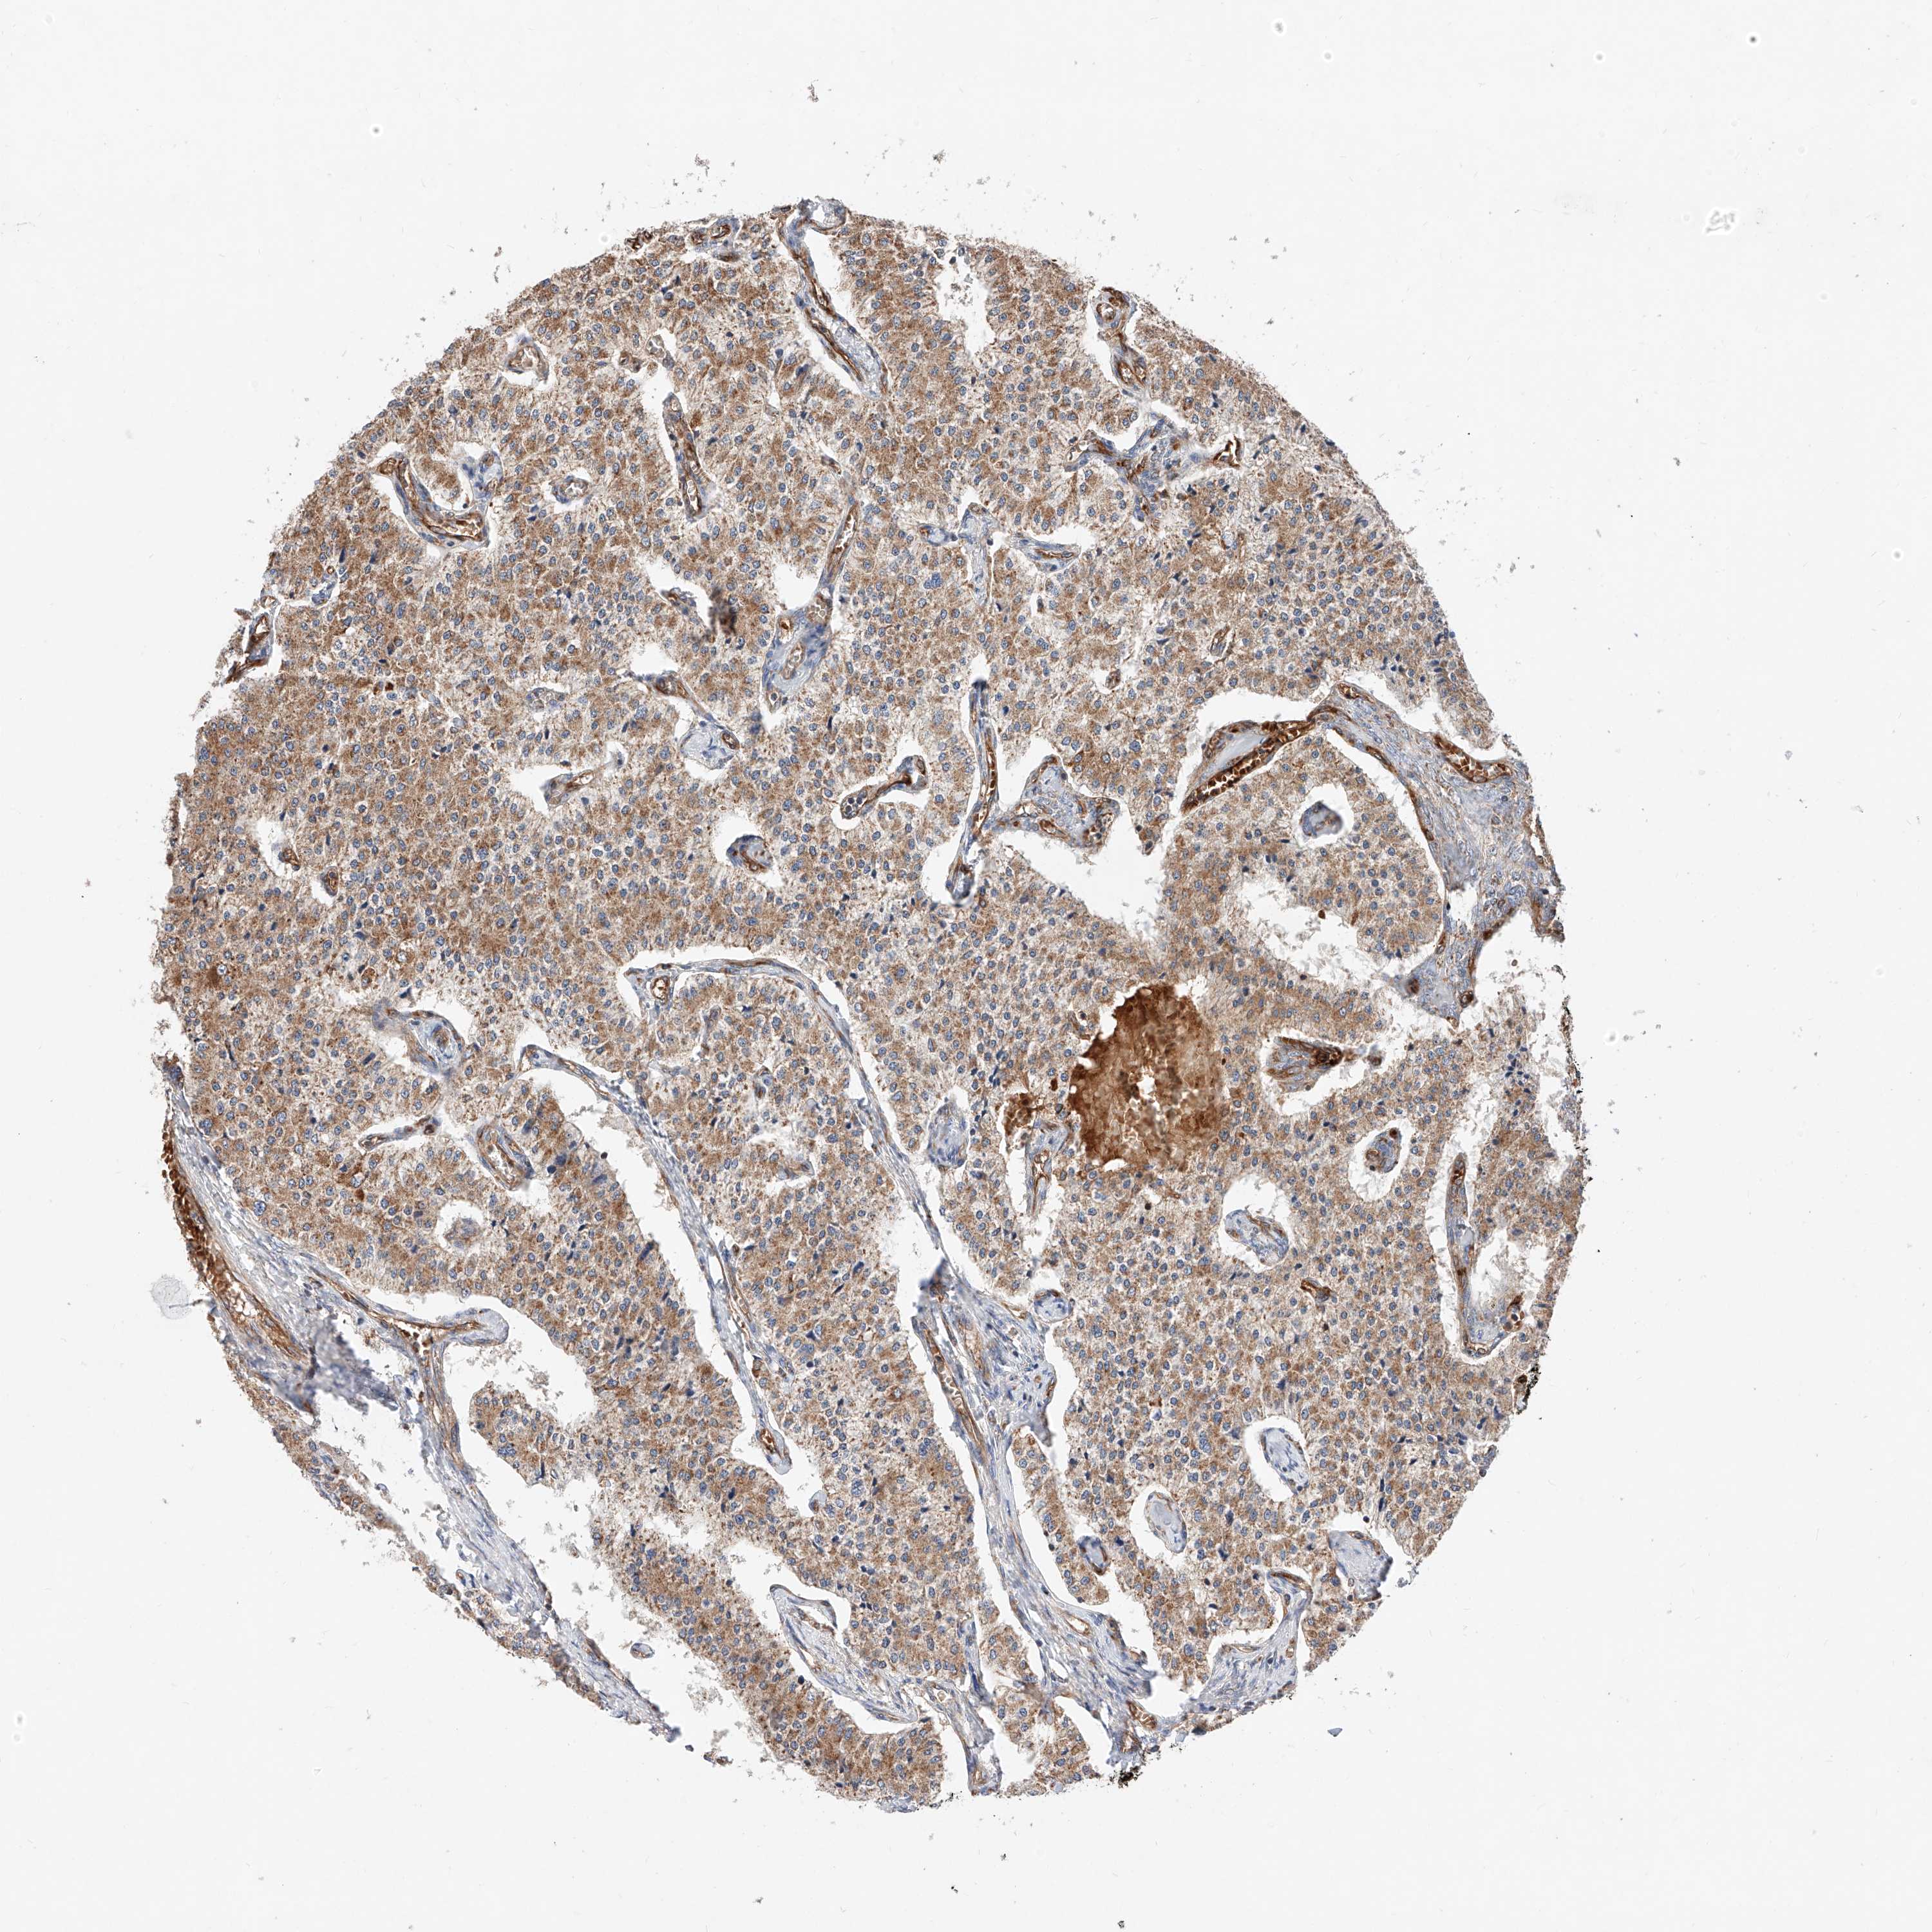

A mouse-over function shows sample information and annotation data. Click on an image to view it in a full screen mode. Samples can be filtered based on level of antibody staining by selecting one or several of the following categories: high, medium, low and not detected. The assay and annotation is described here.

Note that samples used for immunohistochemistry by the Human Protein Atlas do not correspond to samples in the TCGA dataset.

Antibody stainingi

Antibody staining in the annotated cell types in the current human tissue is reported as not detected, low, medium, or high. This score is based on the staining intensity and fraction of stained cells.